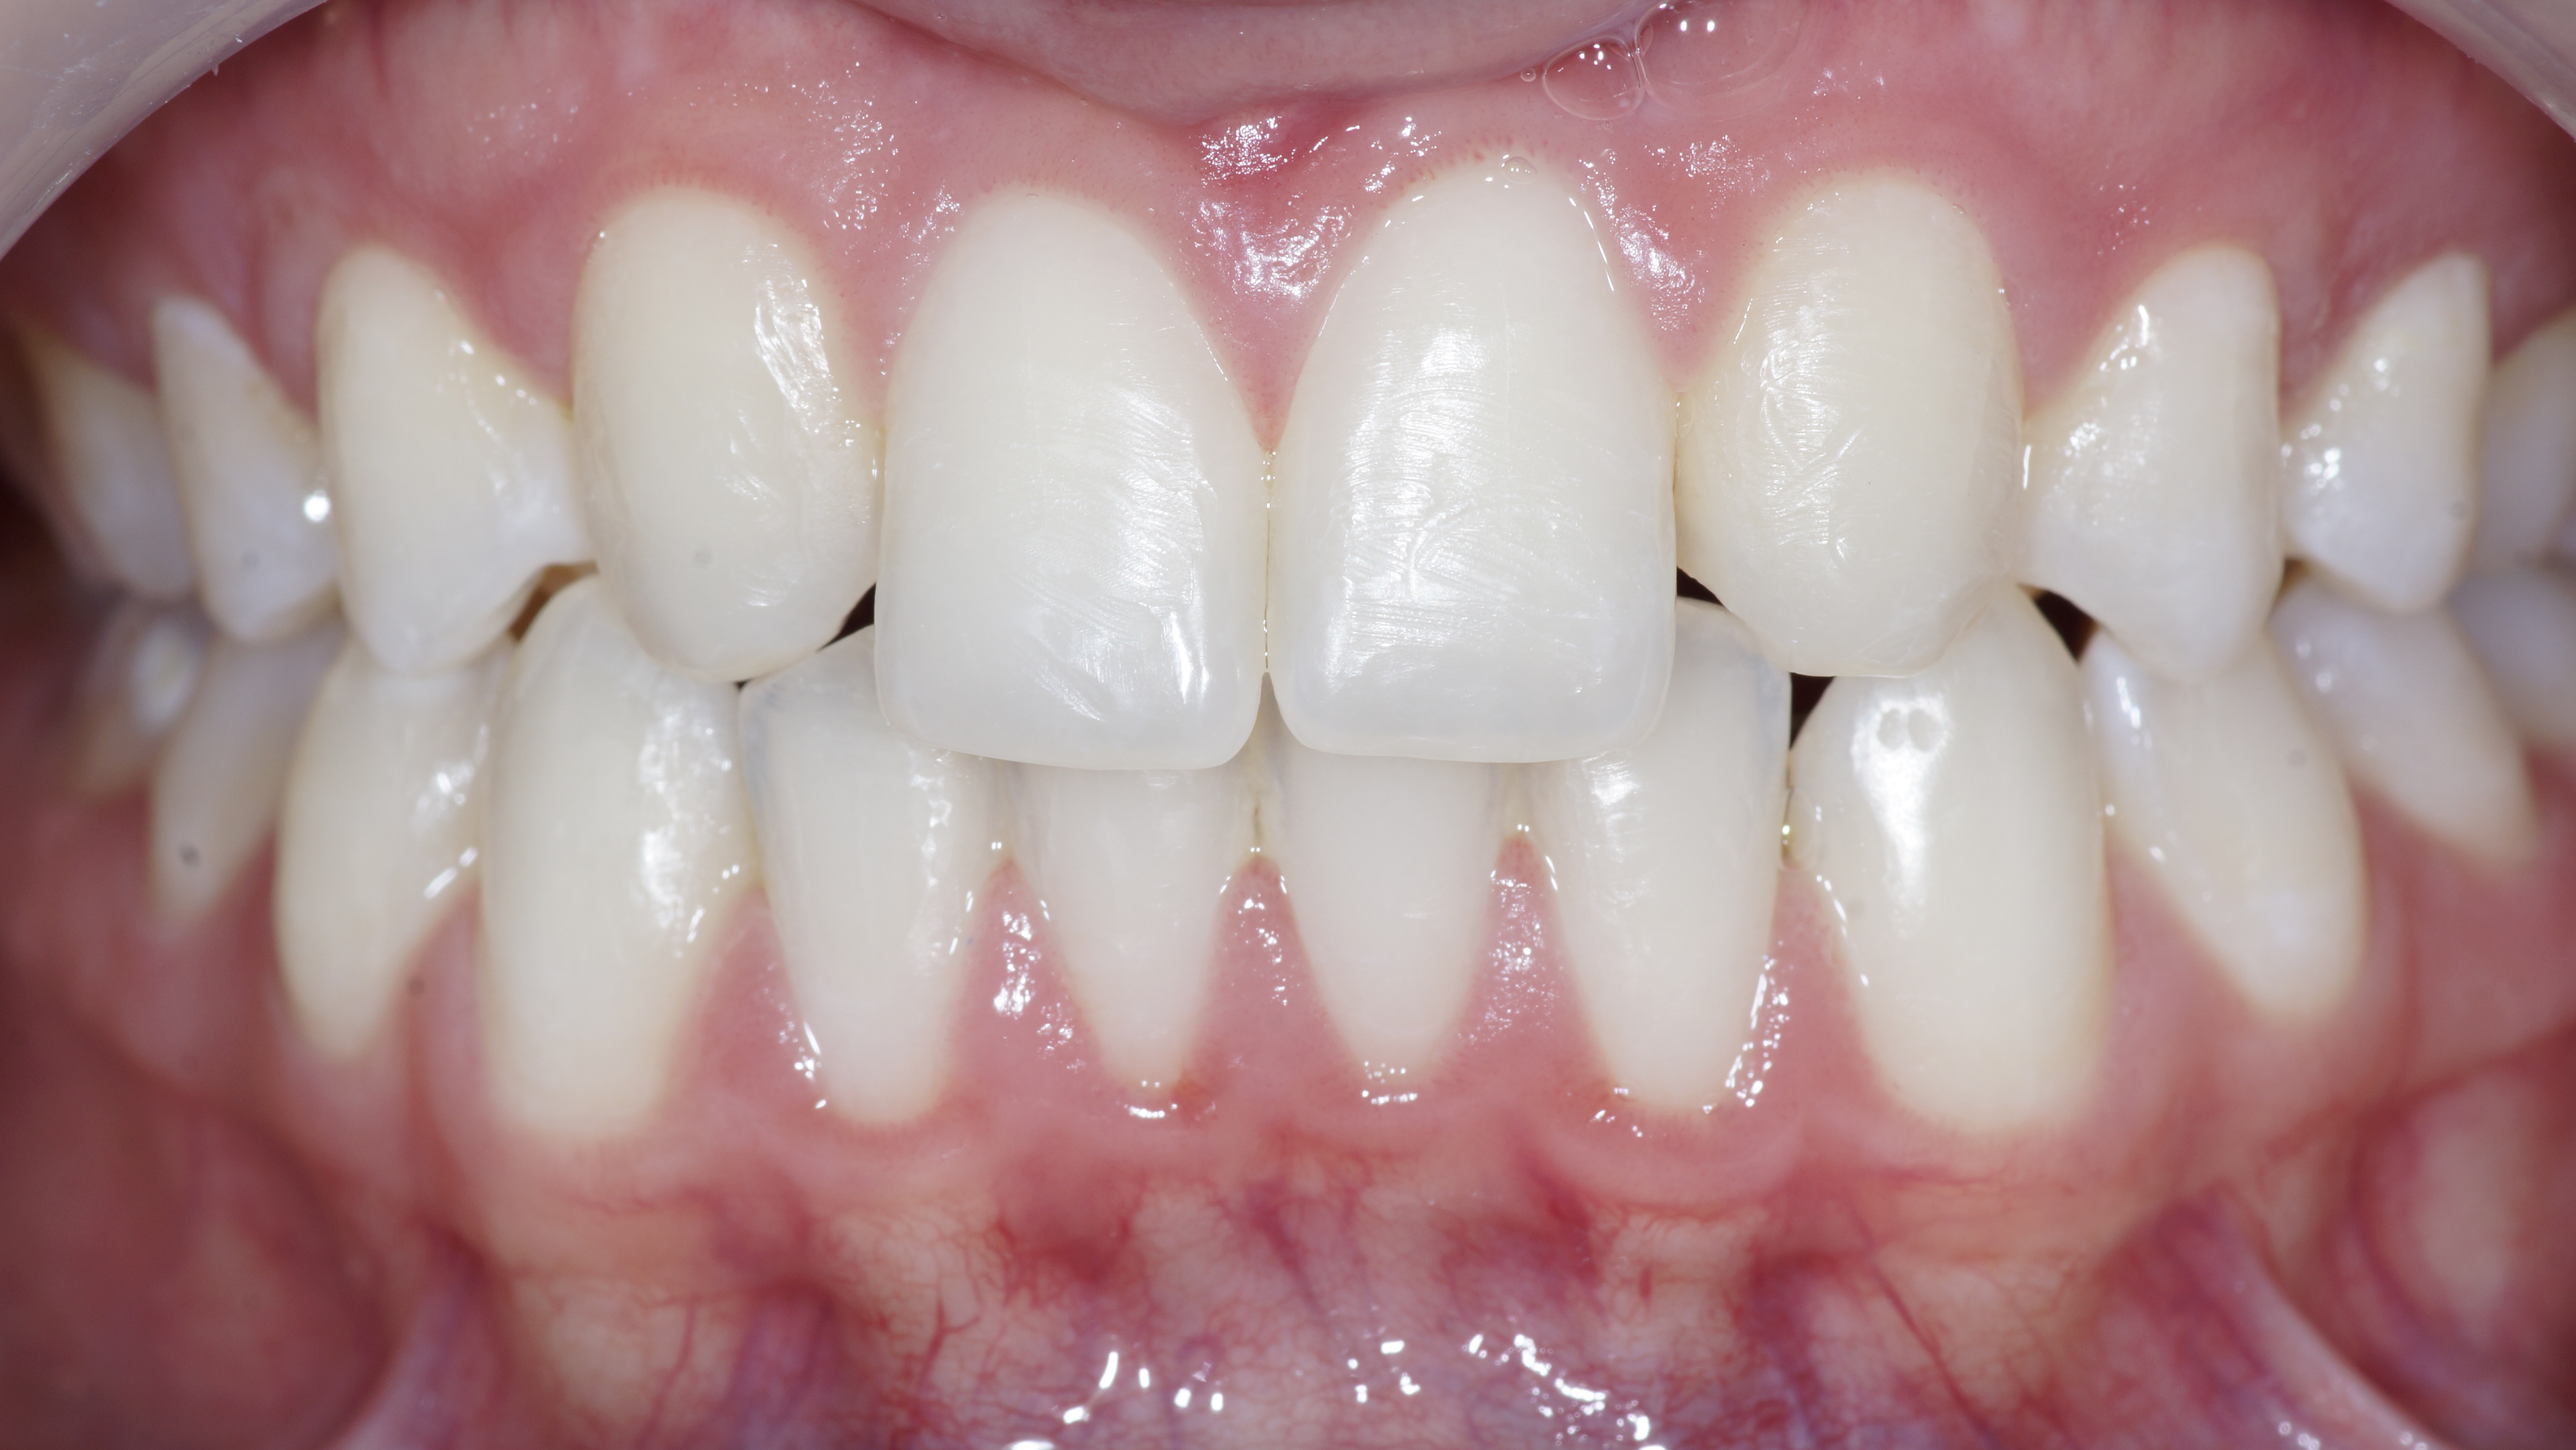

Initial